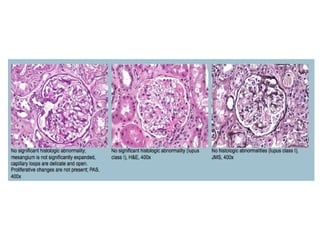

Minimal Change Disease Histopathology:  LM usually discloses no significant abnormalities GBM- unremarkable thickness and texture Mesangium +/- mild expansion Podocytes +/- slightly prominent but no proliferative changes (pseudocrescents)  Proximal tubules may contain prominent protein reabsorption granules The interstitium is usually delicate; foamy macrophages may be seen on rare occasions Acute interstitial nephritis may be seen in association with drug-induced (particularly NSAID-induced) minimal change disease Interstitial fibrosis and tubular atrophy may be seen in elderly patients with comorbid states

Class I lupus nephritis Histopathology:  Light microscopic examination usually discloses no significant abnormalities The glomerular basement membranes are of unremarkable thickness and texture The mesangium may be mildly expanded, but is normocellular The tubulointerstitium is usually unremarkable

Class I lupusnephritis Histopathology: Light microscopic examination usually discloses no significant abnormalities The glomerular basement membranes are of unremarkable thickness and texture The mesangium may be mildly expanded, but is normocellular The tubulointerstitium is usually unremarkable